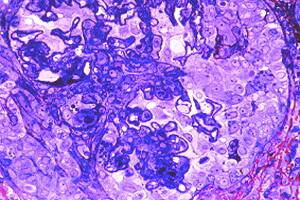

Fig# 12. GNPP III. CA3, CC1 (OMS IVC?):

GNPP III con trombosis, necrosis, proliferación celular. Fibrosis temprana <25%. MOAR 200 X.